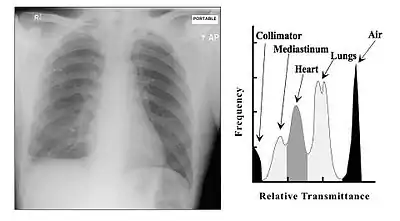

The overall effect of tissue attenuation is illustrated in the Figure 3.9 for the case of a chest radiograph. The exposed area of the patient consists in simplistic terms of air, tissues and bone and is surrounded by the rectangular collimator leaves. The air provides relatively negligible attenuation, while the bone provides substantial attenuation - and tissues provide an intermediate amount. As a result, bone can generate relatively high attenuation at lower X-ray energies and their X-rays shadows can interfere with the visualisation of the lung fields. Increasing the X-ray energy, by increasing the kV, will increase bone penetrability and reduce their shadowing effect. The overall result is a change in the prominence of features associated with different regions in the image histogram.

A typical image is shown in Figure 3.10. It can be seen that bone has a brighter shade of grey than that of the enveloping tissue and is brighter still than the surrounding air. This is the conventional method of displaying a radiograph such that higher photon attenuation is encoded as a brighter shade of grey.